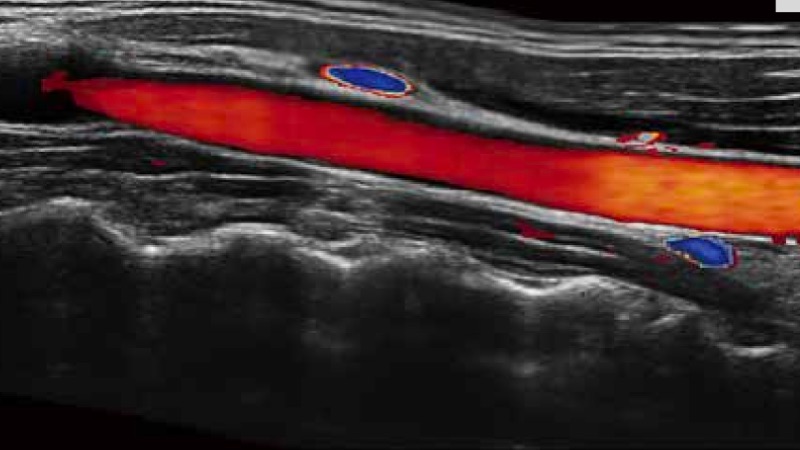

開立醫(yī)療通過不斷的技術(shù)創(chuàng)新,為大眾的生命健康提供持續(xù)關(guān)愛。P12 Plus采用全新一代超聲成像平臺,新平臺旨在將真實還原組織解剖結(jié)構(gòu)作為首要目標(biāo)。平臺采用全新集成化硬件模塊,搭載新一代芯片,系統(tǒng)性能得到大幅提升,為您的診斷提供了豐富的臨床信息。優(yōu)異的圖像表現(xiàn),豐富的探頭配置,全面的應(yīng)用功能,為您日常診斷提供了可靠的助手。

彩色多普勒超聲診斷系統(tǒng)